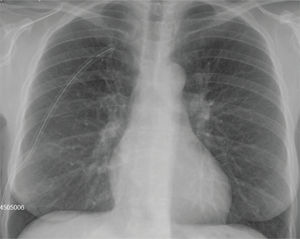

Tras estos hallazgos, se coloca tubo de drenaje torácico y es ingresada en el servicio de cirugía torácica. Tras 24 horas, presenta resolución completa del neumotórax, por lo que se pinza el tubo de drenaje (fig. 2). En la radiografía de control de 24 horas persiste resolución del cuadro, por lo que se retira dicho tubo (fig. 3).